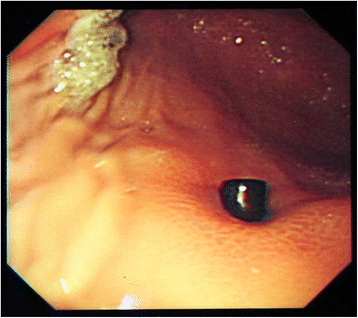

Background: Although foreign bodies (FBs) typically pass spontaneously and uneventfully through the digestive tract, a subset of such bodies may become trapped, eventually leading to significant injury. In particular, the ingestion of magnetic materials can cause serious morbidity due to proximate attraction through the intestinal wall.

Case presentation: We recently treated three pediatric patients who had ingested several magnetic foreign materials. None of these patients exhibited any clinical symptoms or signs suggestive of surgical abdomen. Moreover, it was difficult to determine a definite diagnosis and a treatment plan due to limitations in history taking and radiologic examination. After admission to the hospital, these patients underwent surgery for the following reasons: (1) failure to spontaneously pass ingested foreign materials; (2) sudden-onset abdominal pain and vomiting during hospitalization; and (3) gastric perforation incidentally discovered during gastroduodenoscopy. Subsequently, all patients were discharged without complications; however, their conditions might have been fatal without surgery at an appropriate time.

Conclusions: As the clear identification about the number and characteristics of ingested magnets via radiographic examination or patient history appears to be difficult in pediatric patients, close inpatient observation would be required in any case of undetermined metallic FB ingestion. Patients who are confirmed to have ingested multiple magnets should be regarded as conditional surgical patients, although their clinical conditions are stable.